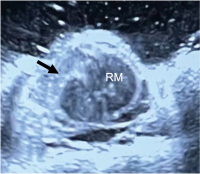

Traumatische spinale Subarachnoidalblutung: ein anschaulicher Fall mit Literaturübersicht // Traumatic spinal subarachnoid hemorrhage with spinal cord compression – a case report and literature review